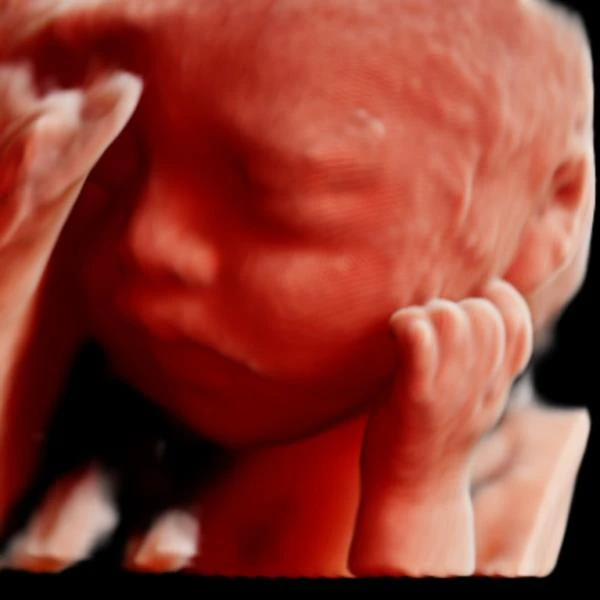

3D/4D Ultrasound Scan

Provides detailed three-dimensional or live video images of your baby, allowing you to see facial features and movements. Enhances visualization for both parents and doctors.